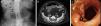

Biliary ileus

Íleo biliar